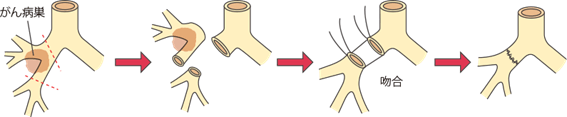

気管支形成術:できるだけ肺を残すために気管支をつなげる

肺の房(肺葉)の根元のところに病巣があった場合、普通に手術をすると片側全部の肺を取ってしまうことになります。

そこで片肺全摘出はできるだけ避けるために、イラストのように根元の気管支の一部分だけを切り取って残りをつなぐことがあります。

技術的には複雑になりますが、肺の機能低下を少なくできます。